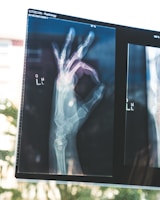

Skräddarsytt ryggimplantat

Patientanpassat ryggimplantat med porösa strukturer som matchar benets densitetsgradienter. Titanlegering med integrerade kanaler för läkemedelsleverans ger snabbare läkning.